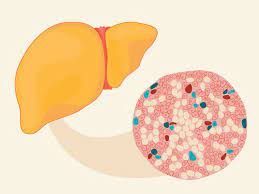

Non-Alcoholic Fatty Liver Disease (NAFLD) and Non-Alcoholic Steatohepatitis (NASH) Treatmen

The treatment approach for Non-Alcoholic Fatty Liver Disease (NAFLD) and its more severe form, Non-Alcoholic Steatohepatitis (NASH), involves lifestyle modifications, medical management, and addressing underlying risk factors